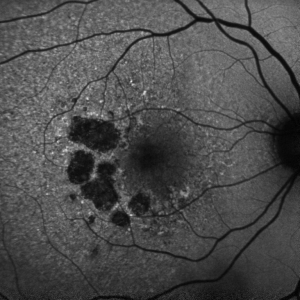

GA is a complex pathophysiologic process that is defined by sharply demarcated atrophic lesions of the outer retina, resulting from the loss of photoreceptors, RPE, and choriocapillaris in the macula.[1] . On fundus evaluation (Figure 1), scalloped areas of hypopigmentation will be found in areas of atrophy with surrounding drusen and pigmentary changes. Fundus autofluorescence (Figure 2) reveals dense hypoautofluorescence due to the lack of lipofuscin following loss of the outer retina and RPE. The amount of perilesional hyperautofluorescence can be used to predict disease progression, with more hyperautofluorescence generally being proportional to the rate of GA growth. Certain patterns of hyperautofluorescence have been implicated in faster disease progression. Optical coherence tomography demonstrates loss of outer retinal layers (outer nuclear layer, ellipsoid zone, interdigitation zone), as well as loss of the underlying RPE and choroidal hypertransmission (Figure 3). In 2017, the Classification of Atrophy Meetings group recommended that non-neovascular AMD trials include color fundus photographs, fundus autofluroescence, near-infrared reflectance, and spectral-domain or swept-source OCT[6], all of which are good tools to help diagnose and monitor disease progression.